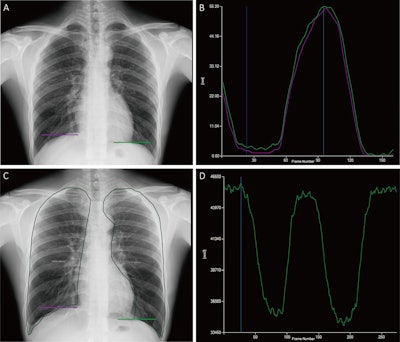

Tracking and quantitative analysis of diaphragmatic motion and projected lung area (PLA) at dynamic chest radiography (DCR) in a 55-year-old healthy man during deep breathing. (A) Posteroanterior radiograph with purple and green lines indicating the right and left lateral diaphragm apices, respectively. (B) Graph of diaphragmatic motion (in millimeters; y-axis) over time (i.e., frame number; x-axis). The software tracked the position of the diaphragm apex at DCR to obtain these amplitude-time plots of diaphragmatic motion (right lung, purple; left lung, green). The dark blue line corresponds to the frame representing the end of inspiration; the light blue line corresponds to the frame representing the end of expiration. (C) Posteroanterior radiograph shows the PLA (outline), which is the area surrounded by the medial edge of the ribs, the diaphragm, and the edge of the mediastinum. (D) Graph of PLA (in millimeters squared; y-axis) over time (i.e., frame number; x-axis). The software automatically tracked the boundaries of the lung fields and obtained the time-varying curves of the bilateral lung field areas. The blue line corresponds to the frame representing the end of inspiration.Tracking and quantitative analysis of diaphragmatic motion and projected lung area (PLA) at dynamic chest radiography (DCR) in a 55-year-old healthy man during deep breathing. (A) Posteroanterior radiograph with purple and green lines indicating the right and left lateral diaphragm apices, respectively. (B) Graph of diaphragmatic motion (in millimeters; y-axis) over time (i.e., frame number; x-axis). The software tracked the position of the diaphragm apex at DCR to obtain these amplitude-time plots of diaphragmatic motion (right lung, purple; left lung, green). The dark blue line corresponds to the frame representing the end of inspiration; the light blue line corresponds to the frame representing the end of expiration. (C) Posteroanterior radiograph shows the PLA (outline), which is the area surrounded by the medial edge of the ribs, the diaphragm, and the edge of the mediastinum. (D) Graph of PLA (in millimeters squared; y-axis) over time (i.e., frame number; x-axis). The software automatically tracked the boundaries of the lung fields and obtained the time-varying curves of the bilateral lung field areas. The blue line corresponds to the frame representing the end of inspiration.RSNAAccording to the analysis, bilateral (right and left lung) ΔPLA during deep breathing on DCR correlated well with FEV1 percent predicted (r = 0.65; p